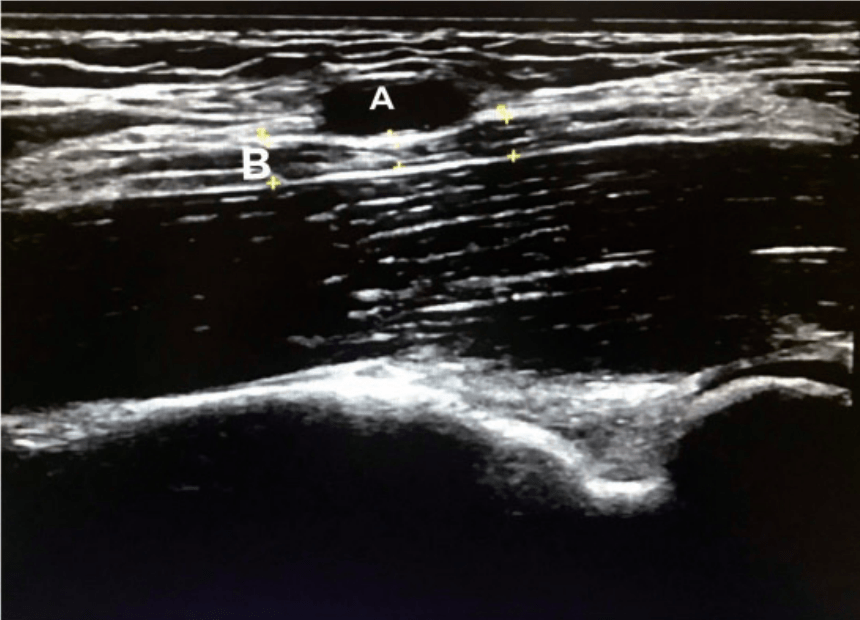

Median nerves and arteries

Stimulated by Liu et al 2020,[1] and Li et al 2021.[2] Figure 1 from Liu et al 2020.[1]A – superficial brachial arteryB – median nerve EBM – evidence based medicineMR angiography – magnetic resonance angiographyPMA – persistent median arterykey to acronyms These are a couple of recent papers, a case report and a letter with … Continue reading Median nerves and arteries